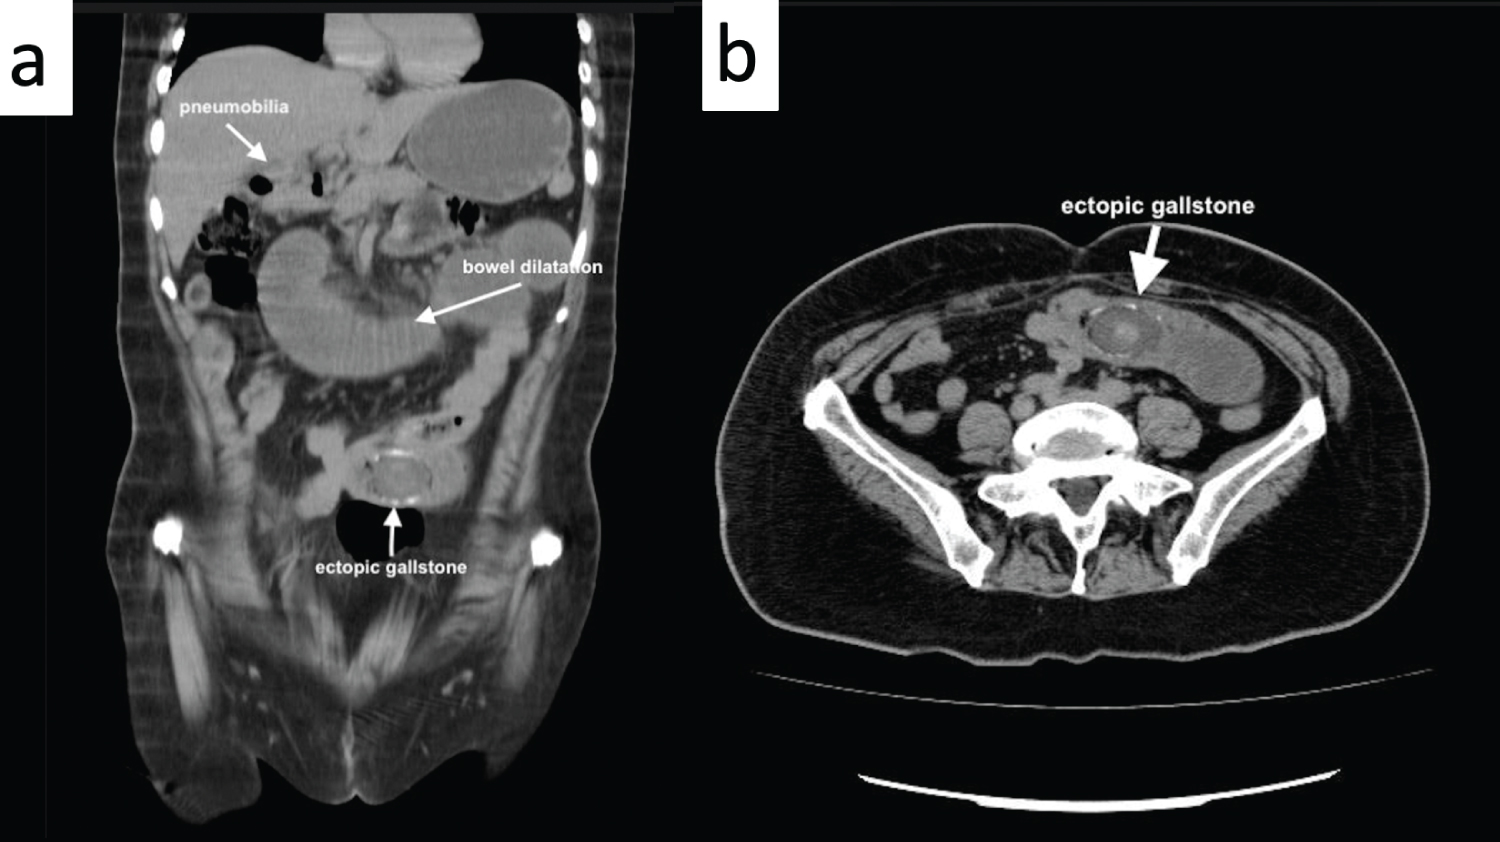

Radiological examinations were performed, the CT scan demonstrated an ectopic, obstructing, partially calcified jejunal intraluminal stone, with approximate dimensions of 4 × 4 cm, signs of small bowel obstruction with dilated jejunal loops above the obstruction, and signs of incipient pneumobilia "Rigle's triad" (Figure 1).

Figure 1: a) Ectopic gallstone; b) Rigler's triad; ectopic gallstone, bowel dilatation, pneumobilia. View Figure 1

Radiological signs associated to GSI are Rigler's triad; pneumobillia or contrast material in the biliary tree, small bowel partial or complete obstruction signs (air-fluid levels, dilated small bowel loops), ectopic gallstone (usually right iliac fossa). The presence of two of the three signs is considered pathognomonic and it presents in 20%-50% of cases [2,5,12]. Petren sign described as the presence of air or oral contrast in gallbladder or biliary tree secondary to the transfection of the contrast agent from the fistula tract can also be identified. Another radiologic pattern is the Forchet sign (after oral contrast enhancement), which is the "snake head like" shape of the bowel lumen due to the obstruction, being unable of the contrast agent to pass the stone, and accumulate [2]. Endoscopy can be a useful adjunct to imaging studies for diagnosis and management of this condition [2,5,6].